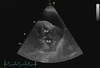

48

A 11-year old male castrated Golden Retriever presents for collapse with muffled heart sounds on examination. You ultrasound the heart and obtain the following image; the right atrium (RA) and right ventricle (RV) are labeled. A large mass is seen in the right atrioventricular groove with pericardial effusion. What is the likely diagnosis? Hemangiosarcoma Lymphoma Chemodectoma Idiopathic pericardial hemorrhage Pulmonary adenocarcinoma

Answer: Hemangiosarcoma. Explanation The correct answer is hemangiosarcoma. Hemangiosarcoma of the heart has a predilection for the right auricle of dogs, with Golden Retrievers being predisposed. Stabilization of this patient will require pericardiocentesis; prognosis is guarded and may include chemotherapy, pericardiectomy, or rarely auriculectomy. Chemodectoma arises from the ascending aorta and heart base; lymphoma is rare in the heart of dogs and is more commonly metastatic than a single mass. Idiopathic pericardial hemorrhage is incorrect because of the clear evidence of a mass. The likely diagnosis is hemangiosarcoma. Hemangiosarcoma often affects the right auricle in dogs, with Golden Retrievers being predisposed. Stabilization involves pericardiocentesis; prognosis is guarded and may involve chemotherapy, pericardiectomy, or rarely auriculectomy. Chemodectoma arises from the ascending aorta and heart base. Lymphoma in the heart is rare and typically metastatic. Idiopathic pericardial hemorrhage is excluded due to the evident mass.